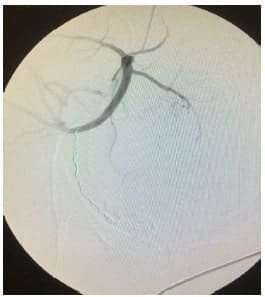

El éxito en general de la embolización, que se refiere a la oclusión completa de los vasos elegidos (figura 6), oscila entre el 85 y 95 % 10, y en este trabajo fue del 100 %.

La embolización ha demostrado en diferentes estudios disminuir estancias hospitalarias, incluidas las de cuidado intensivo, necesitando únicamente en un 25 % de casos este recurso 25.

Figura 6. Resultado exitoso con oclusión completa de las ramas elegidas, preservando las arterias glútea y vesical.